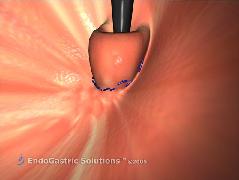

Η ανάγκη για μιά νέα μέθοδο αντιμετώπισης της ΓΟΠΝ, ισάξιας αποτελεσματικότητας με την Nissen αλλά χωρίς τους περιορισμούς και τα προβλήματα της, οδήγησε στη δημιουργία διαφόρων ενδοσκοπικών μεθόδων, οι οποίες στην πλειοψηφία τους απέτυχαν. Εξαίρεση αποτελεί η διαστοματική θολοπλαστική EsophyX. Η μέθοδος EsophyX είναι μία χειρουργική τεχνική όπου η γαστροοισοφαγική βαλβίδα διορθώνεται από το εσωτερικό του στομάχου. Με χρήση γενικής αναισθησίας η συσκευή εισάγεται από το στόμα (εικ.1), με την βοήθεια γαστροσκοπίου, και φθάνει στο στομάχι ενδοαυλικά (εικ.2). Με ανάστροφη όραση γίνεται συρραφή και επανακατασκευή της γαστροοισοφαγικής συμβολής με ειδικά clips που τοποθετούνται σε όλο το πάχος του τοιχώματος του στομάχου (εικ.3). Όταν υπάρχει μικρή διαφραγματοκήλη ανατάσσεται με την εισαγωγή και τοποθέτηση του οργάνου.

Εικόνα 3: Συρραφή και επανακατασκευή της γαστροοισοφαγικής συμβολής με ειδικά clips που τοποθετούνται σε όλο το πάχος του τοιχώματος του στομάχου